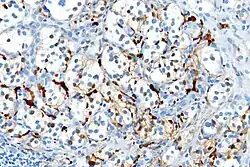

With immunohistochemistry, the chief cells located in the cell balls are positive for chromogranin, synaptophysin, neuron specific enolase, serotonin, neurofilament and Neural cell adhesion molecule; they are S-100 protein negative. The sustentacular cells are S-100 positive and focally positive for glial fibrillary acidic protein. By histochemistry, the paraganglioma cells are argyrophilic, periodic acid Schiff negative, mucicarmine negative, and argentaffin negative.

S100 immunostain highlighting the sustentacular cells in a paraganglioma -